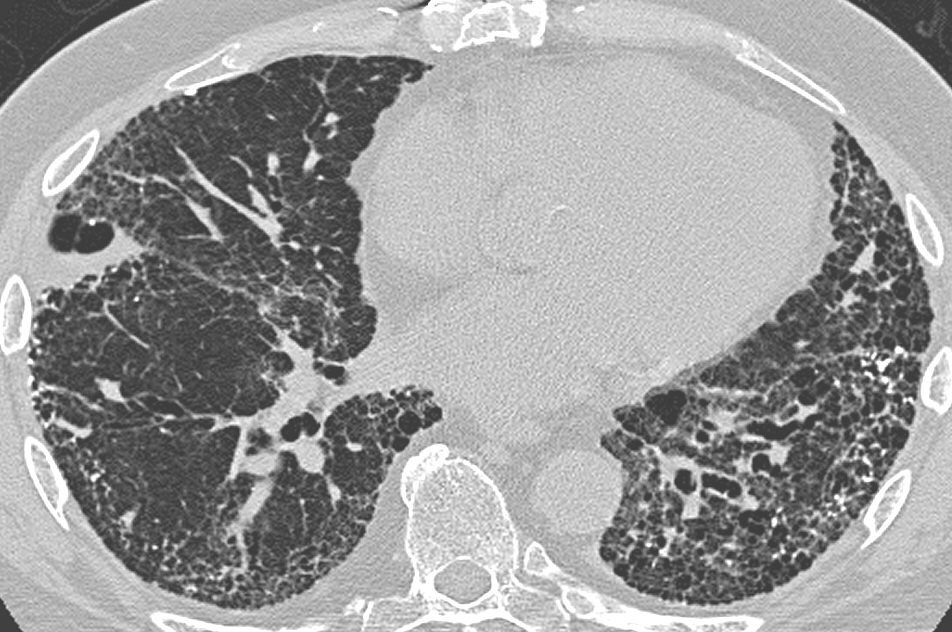

Los escaneos de TC de baja dosis son muy útiles para detectar el cáncer de pulmón en fases poco avanzadas. Esta técnica emplea menos radiación y no requiere la inyección de un tinte de contraste. Pero el diagnóstico es muy difícil, lo que implica una alta tasa de falsos positivos y demasiados procedimientos médicos innecesarios.

Los datos de las imágenes empleadas en competición procedieron del Instituto Nacional del Cáncer de Estados Unidos. El director del reto, Keyvan Farahani, asegura que reducir el número de falsos positivos en los diagnósticos de cáncer de pulmón basados en imágenes de TC de baja dosis marcaría una importante diferencia para los pacientes. Se detectan alrededor de 222.500 casos nuevos de cáncer de pulmón en Estados Unidos cada año, según la Sociedad Estadounidense para el Cáncer.